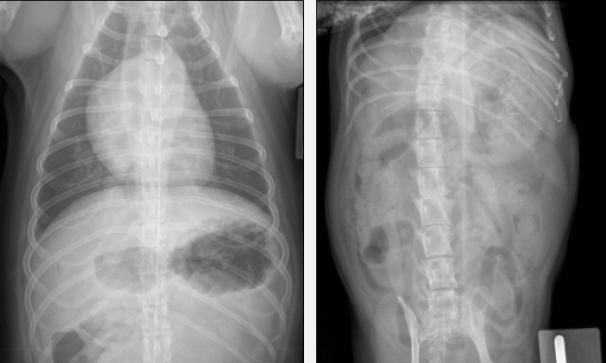

Dire quelle image de l’estomac correspond à un chat et laquelle correspond à un chien

à droite = chat

à gauche = chien

*Chez le chien, l’estomac a une forme moins repliée et l’antre pylorique se retrouve à droite. Chez le chat, l’estomac a une forme de « U » abrupte et l’antre pylorique reste généralement plus proche de la ligne médiane de l’abdomen.